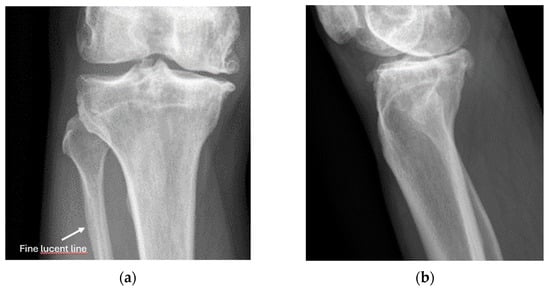

4.2. Sonoanatomy of Fractures [Figure 5, Figure 6, Figure 7 and Figure 8]

- Irregularity, interruption, or gaps in the cortical line: the cortical bone normally appears as a continuous, bright echogenic line, which is interrupted or irregular in the presence of a fracture.

- Bulging or abnormal angulation of the cortical layer: deformities or outpouchings of the normally straight cortical surface indicate displacement or bending at the fracture site.

8.1. Screening of Patients with Suspicion of Fracture to Improve the Specificity of X-Rays [Figure 9 and Figure 10]

- Recommendation 1: Ultrasound should be used as a screening tool for suspected fractures, followed by further imaging (X-ray or CT) if necessary. In cases of obvious simple fractures, conventional X-ray remains the preferred method.

8.2. Screening of Patients with Suspicion of Occult and Stress Fractures (Figure 11 and Figure 12)

- Recommendation 2: Given the promising but limited evidence, ultrasound should be considered a first-line imaging tool for suspected occult fractures, except in the pelvis and vertebral column.